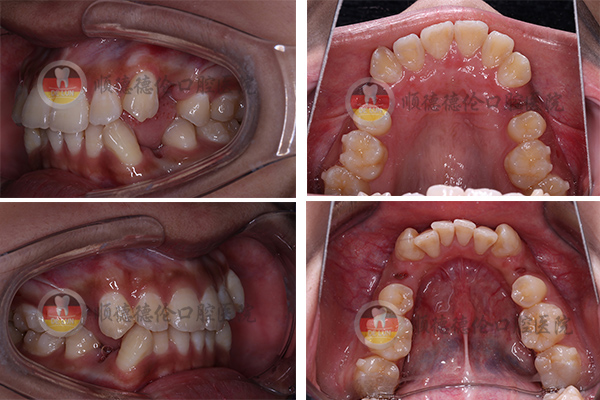

牙齒狀況:牙齒外突、擁擠、不整齊

3、拍口內(nèi)照

上下兩排牙齒共拔了8顆牙齒,為了變美我也是拼了(⊙o⊙)

我的方案是要拔牙的,說出來估計(jì)會(huì)嚇到別人,因?yàn)槲野瘟?顆,分三次拔完了,估計(jì)很少有人能夠理解,周圍不少朋友說我瘋了,我是想美想瘋了,哈哈哈……